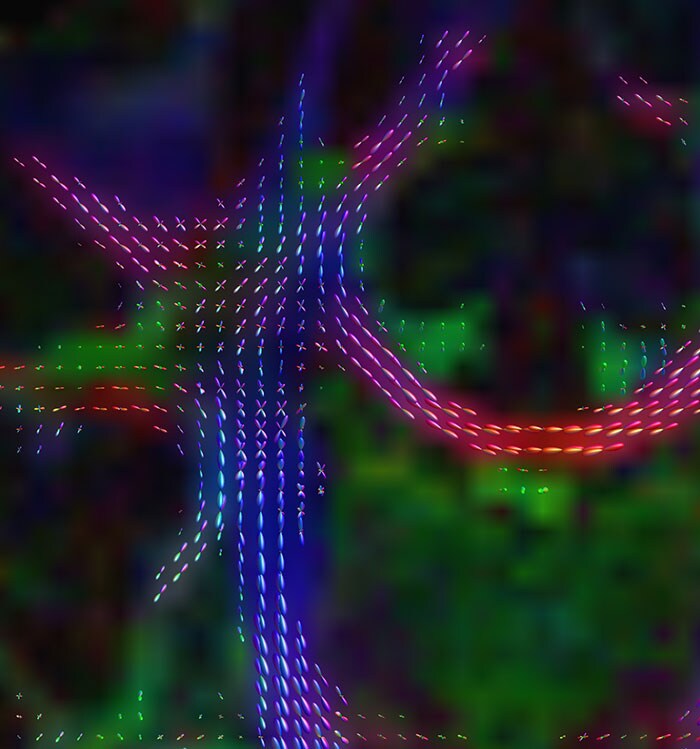

These images are produced using the ABCD protocol and illustrate the use of more sophisticated and accurate models of diffusion. The color FA maps are shown for reference. The diffusion tensor model represents the diffusion within each voxel as an ellipsoid.

Alternative models, such as constrained spherical deconvolution, better capture the rich information available with the use of high b-value dMRI and many sampling directions. In much of the brain, voxels contain multiple white matter tracts, and it is essential to capture this information to be able to perform accurate tractography and generate diffusion connectomes.

Diffusion acquisition on Achieva 3.0T dStream with matrix 140x141, 81 slices, FOV 240x240 mm, voxels 1.7x1.7x1.7 mm, TR 5300 ms, TE 89 ms, flip angle 78, MultiBand SENSE factor 3, partial Fourier 0.645, 102 diffusion directions, b-values 0 (6), 500 (6), 1000 (15), 2000 (15), 3000 (60) , scan time 2x 4:37 min. Images provided by Dr. Watts.